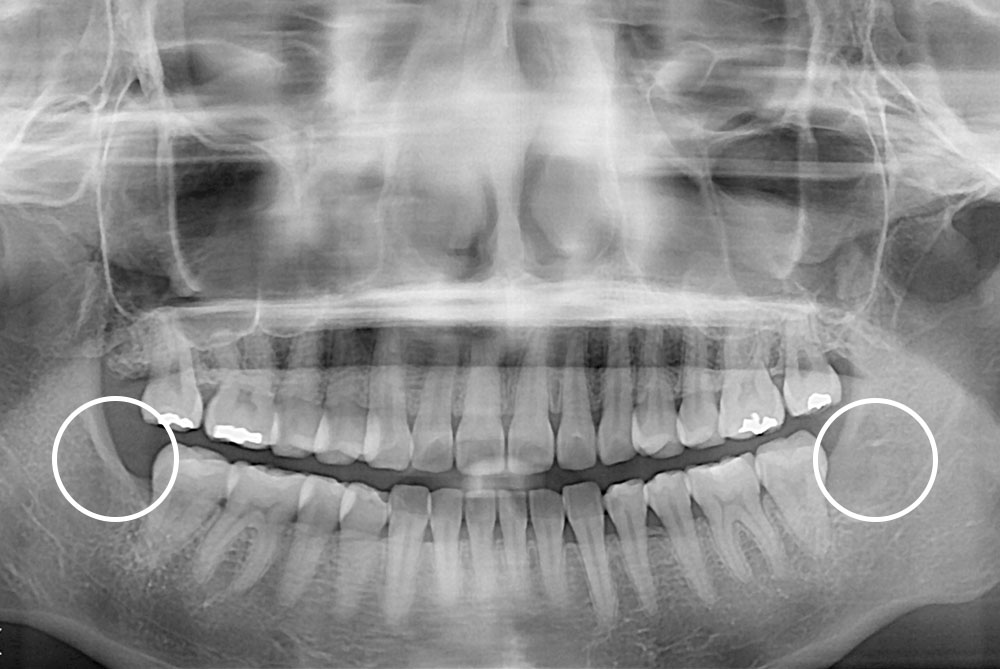

[사랑니] 매복 사랑니 발치

치료전 : 2018-07-27